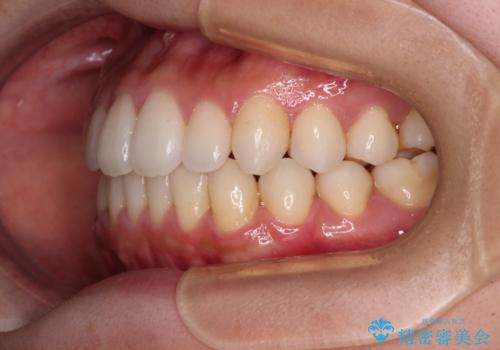

インビザラインで口を閉じやすく

- 下唇に上の前歯が当たることを気にして来院された患者様です。

上顎の親知らずを抜去し、歯列全体を後方に移動させるとともに、IPR(歯と歯の間を削る)を行うことで口元の閉じにくさを改善していくこととしました。

咬合力が強く、マウスピースを介した咬み込みが顕著であったため、奥歯の咬みにくさやIPRのスペースが改善しにくく、治療期間が思った以上にかかってしまいました。